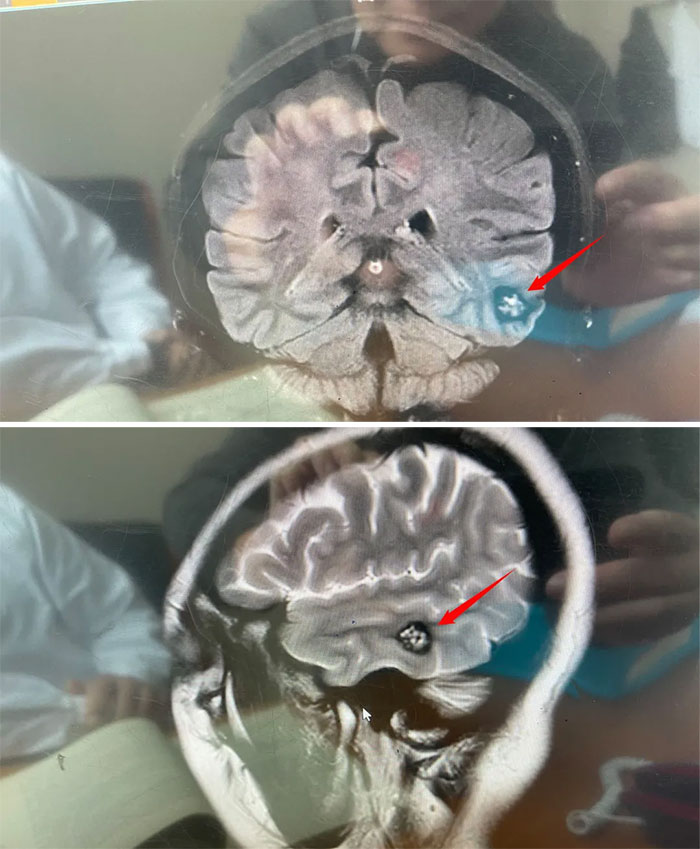

医院神经外科6A病区侯增欣主任团队为林女士完善相关检查,头颅磁共振显示:左侧颞叶见类圆形局灶性异常信号灶,约1.5*1.7*1.2cm。灶心“蜂窝状”,灶内微量出血(亚急性期)。

▲病灶灶心呈“蜂窝状”